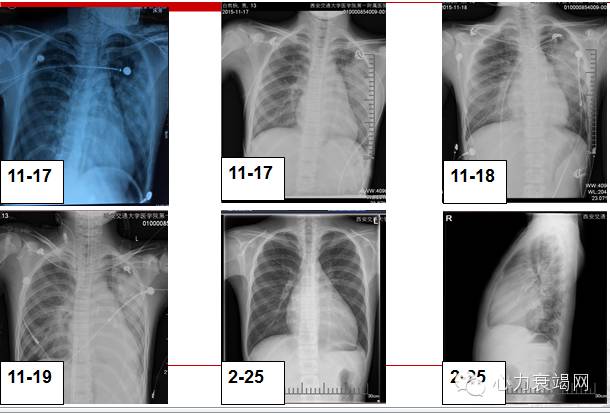

近3月来心脏结构和功能变化:

3月来胸片变化

第二次住院(2016-2-25)

随访过程中发现,间断感胸闷、气短,近几日出现夜间咳嗽、腹胀,再次入院。

入院查体:心界左下大,心率100次/分;肝肋下3cm.出院后给予利尿、扩管、强心、抑制心室重构、营养心肌治疗。